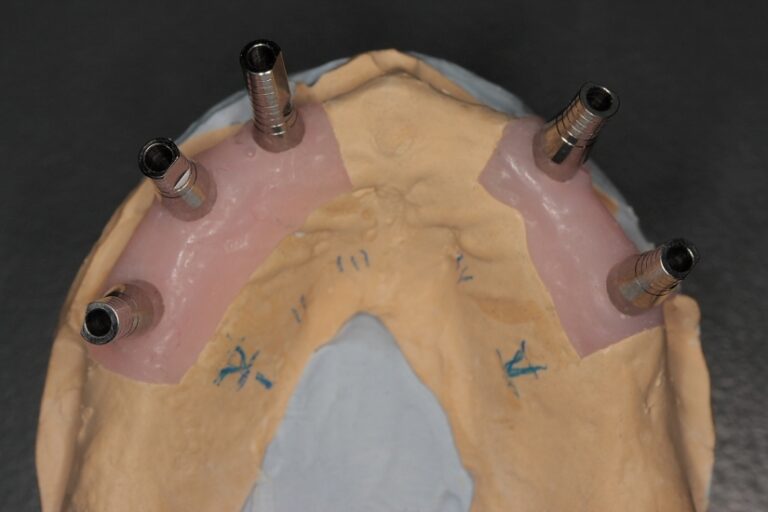

Photo 5a, b. Finished structure is fixed with the screws.

The work satisfying patient’s every esthetical and functional requirements was performed with the help of Alpha Dent Adapters notwithstanding complicated clinical conditions (Photo 6а, b, c and d).